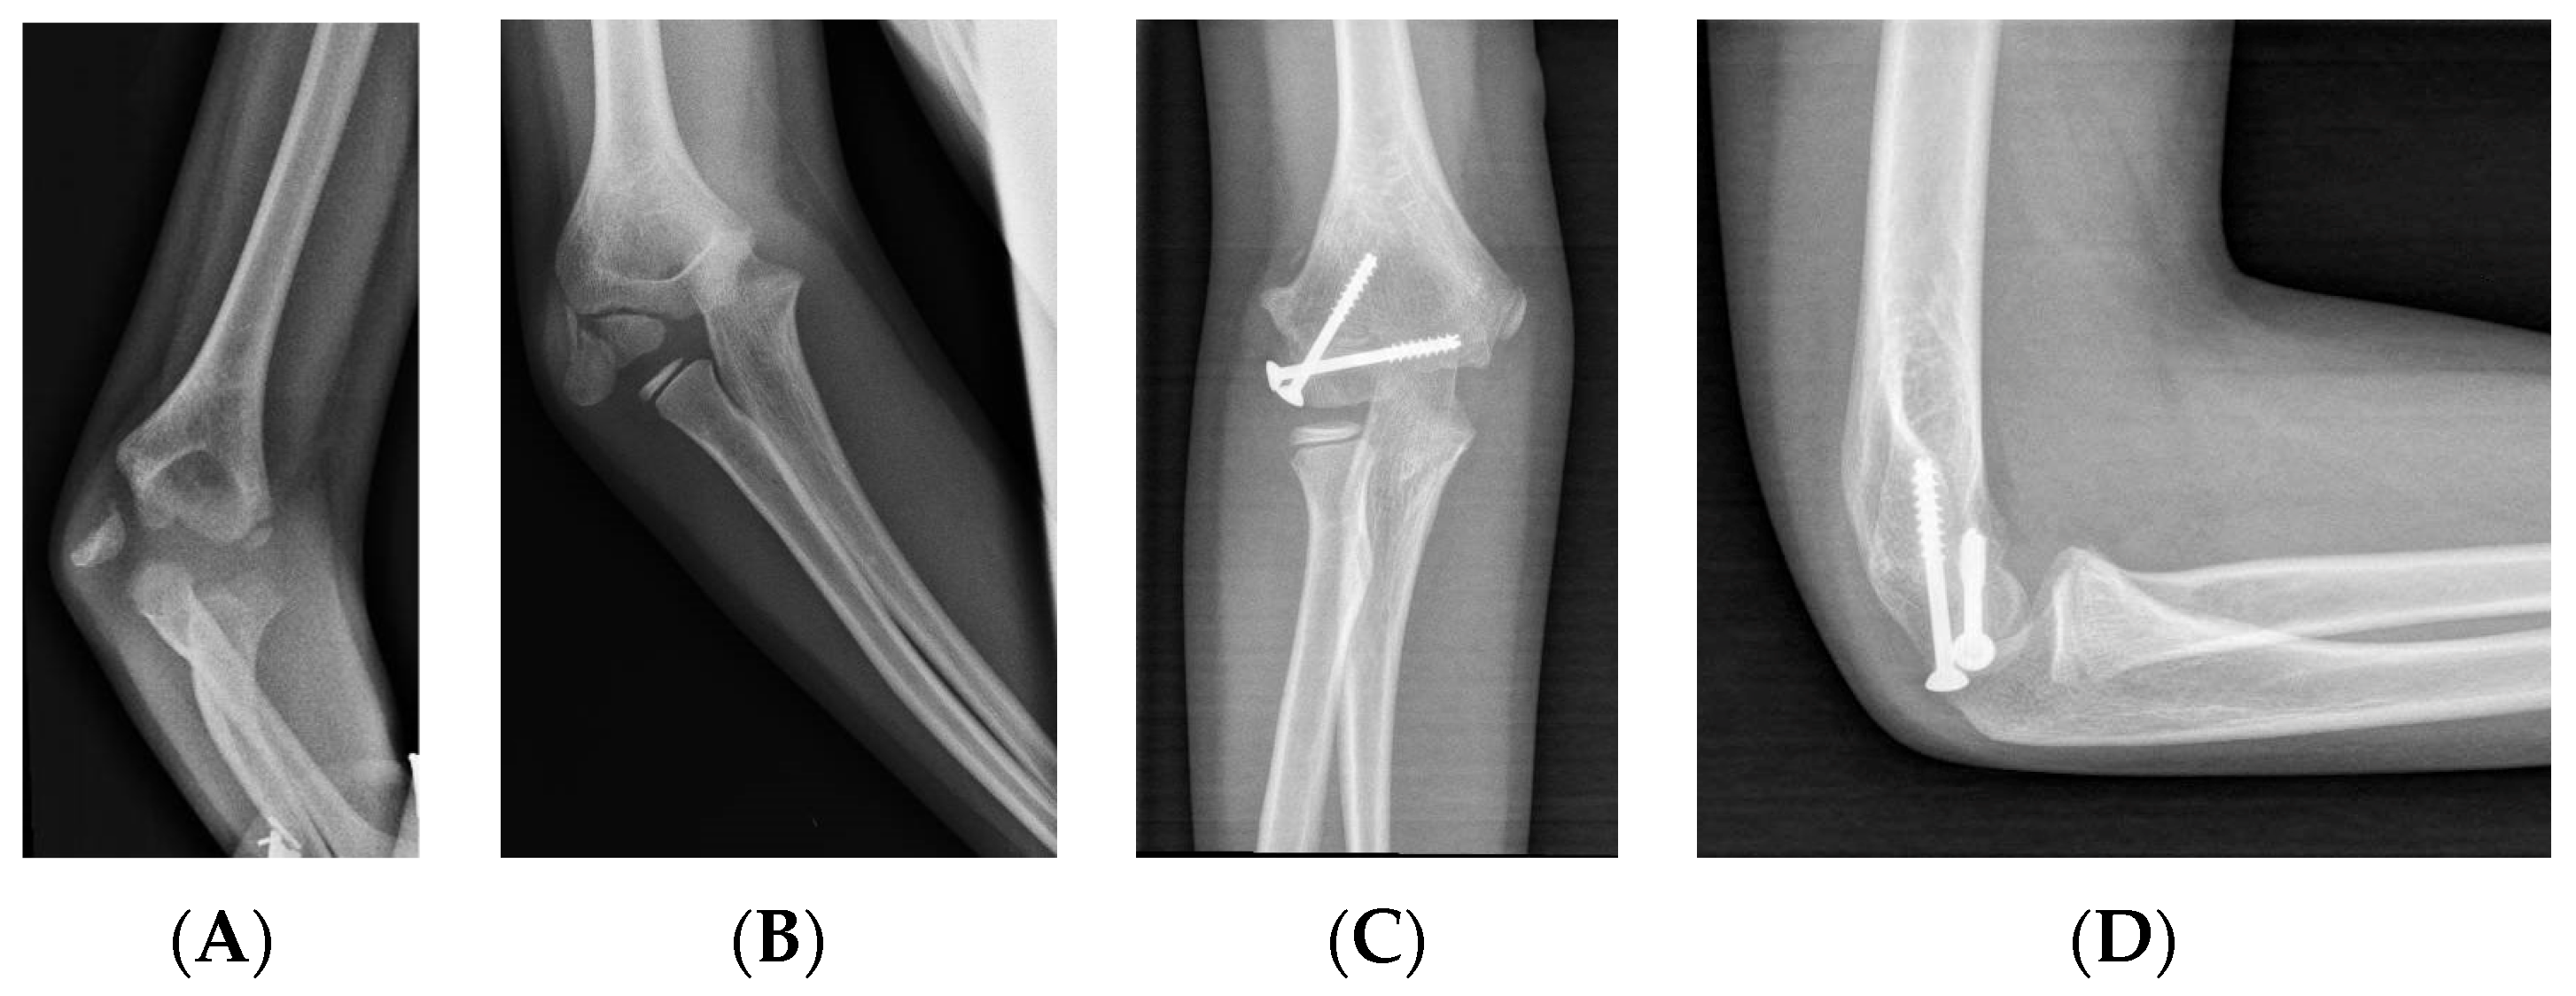

3.2.5. Fixation: Cannulated Screws

While K-wires allow for limited compression, cannulated screws offer a more favorable alternative in this regard and can be used in patients with a sufficiently long metaphyseal fragment [31] (Figure 4).

Figure 4.

LHC fracture with >2 mm displacement and rotated fragment. (A) AP view. (B) Lateral view. (C) Treatment with two cannulated compression screws, AP view. (D) Treatment with two cannulated compression screws, lateral view.

During closed reductions, the screw is inserted percutaneously, while in open reductions, it can also be inserted through the incision. Stein et al. (2017) argued in their work that the use of cannulated screws with closed reduction and percutaneous synthesis offers good results and avoids the complications of the open approach [42].